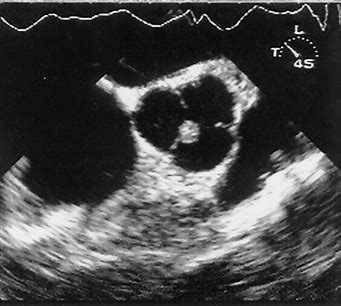

What cardiac condition is demonstrated in this image?

LA myxoma

Lipoma

LA thrombus

Angiosarcoma

Rhabdomyosarcoma